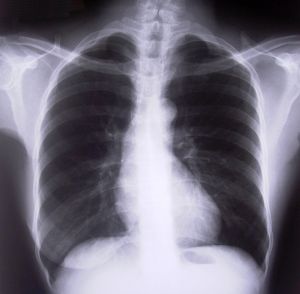

Our Boston disability lawyers know that lung cancer symptoms can include coughing, difficulty breathing, chest pain, chronic respiratory infections and many other serious health effects. The respiratory process affects almost all of the systems in the body, so a person suffering from lung cancer may be unable to do many activities of daily living as well as many tasks that would be required to work. The cancer also typically necessitates invasive and aggressive treatment, including surgery, chemotherapy and radiation. All of these treatment methods can have debilitating side effects.